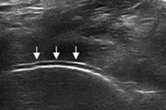

“双轨征”

跖趾关节软骨表面可见高回声不规则增强的软骨滑膜边缘线,呈“双轨征”。

高回声带

软骨表面回声增强,与深面的骨性关节面强回声线形成“双轨征”。

聚集体

髁软骨的双轨征状,显示髌腱内部的聚集体

肌骨超声可通过高清影像图判定软骨表面有无出现一条与强回声骨皮质平行的线样强回声,即“双轨征”这一痛风性关节炎特征性表现,判定疾病所属。当尿酸盐粘附并沉积于漂浮的滑膜上时,超声检查可在关节腔内发现漂浮的高亮回声;而当尿酸盐长期沉积于韧带上时,在超声中即显示条带状的略高回声(韧带)中出现高回声点、高回声带或高回声团块(尿酸盐),从而判断痛风病情处于哪一时期。